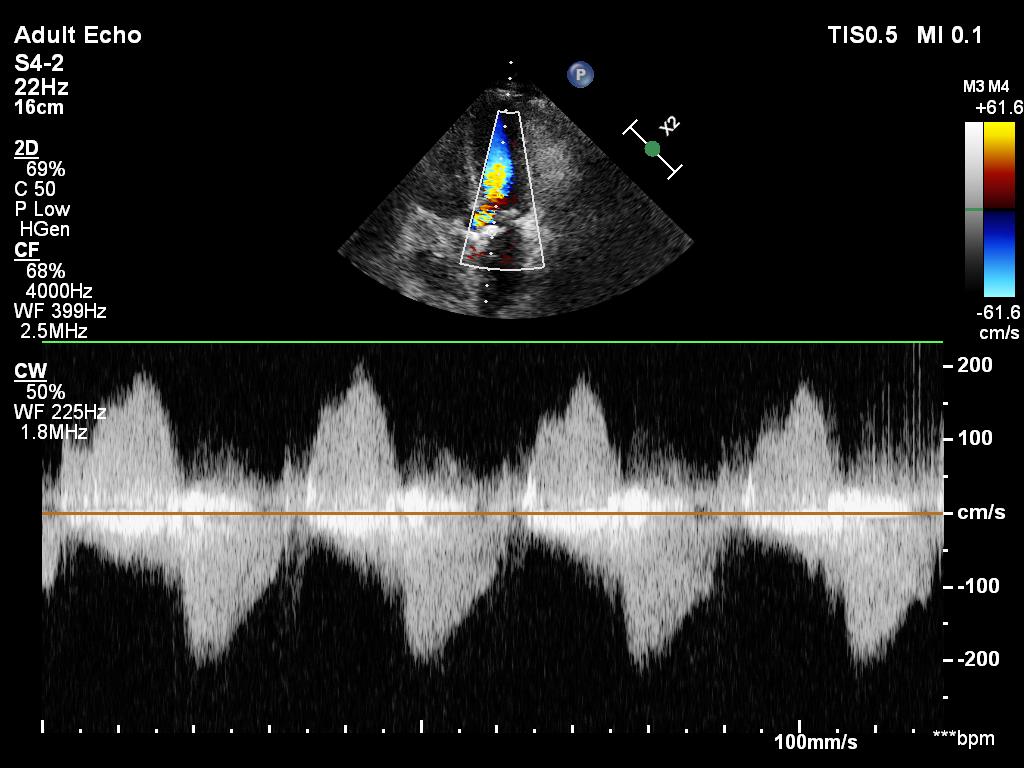

First quiz time:

What do these numbered traces represent on this LV CW doppler trace?

4/ A4C w/ colour

The first quiz pic shows

1) mitral regurgitation - probably only mild

2) flow across the aorta - aortic stenosis?

3) intraventricular obstruction

Let's look at the last two detail